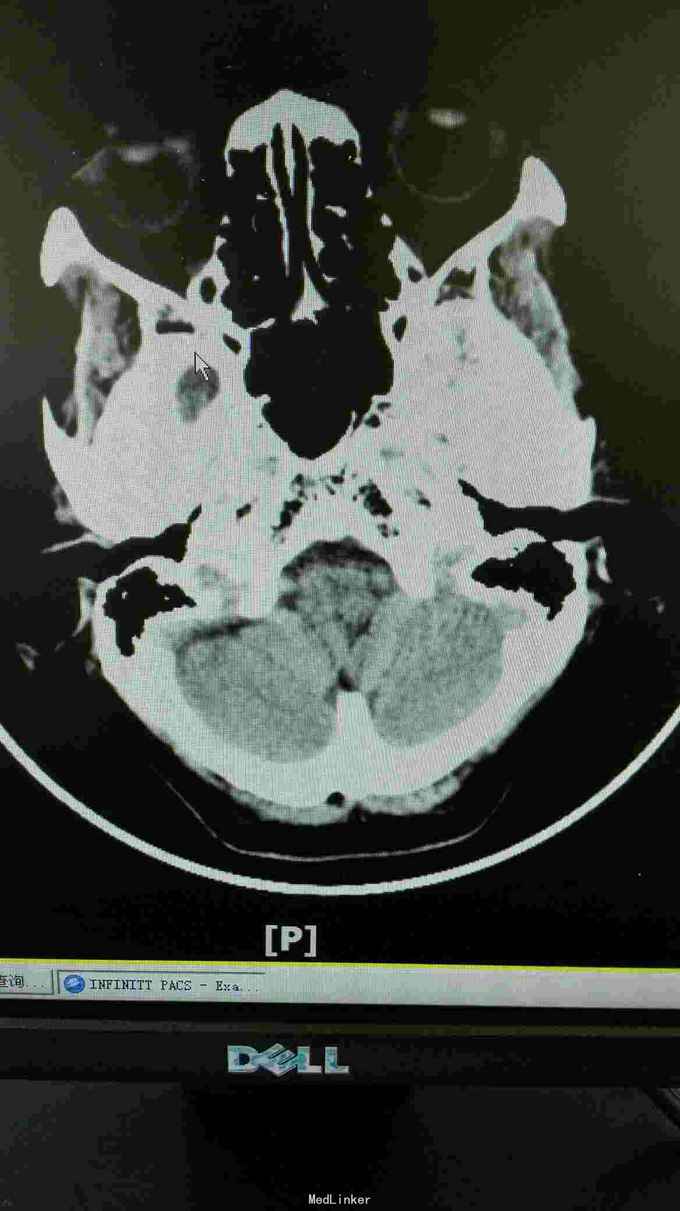

这患者优先考虑重症肌无力,但是以单侧为主,所以动眼神经麻痹也需要排除,因为患者在上级医院做过“新斯的明试验”症状稍改善,持续数小时后又加重,所以等药效过了之后给她做了肌电图,重频试验阴性。1-5波幅下降不明显,结合头颅CT结果,诊断重症肌无力,予新斯的明口服后症状是有改善, 我想请教各位,单单从症状和新斯的明试验可以诊断重症肌无力吗?因为这个病人的肌电图表现是阴性的胸部CT也没看到有胸腺增生。